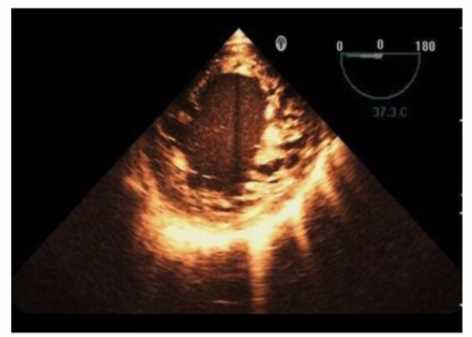

Which finding is shown in this image?

1. Chiari network

2. Left atrial thrombus

3. Cor triatriatum

4. Artifact

Answer(s): A

Explanation:

The echocardiographic image shows a mobile, highly echogenic, mesh-like structure within the right atrium consistent with the Chiari network. The Chiari network is an embryologic remnant of the right valve of the sinus venosus, appearing as a fenestrated, reticulated membrane that is usually thin and mobile, found near the orifice of the inferior vena cava or the coronary sinus.

This structure is benign and often an incidental finding but can be confused with thrombus or atrial tumors. Unlike left atrial thrombus, which appears as a more solid, immobile mass often located in the left atrial appendage, the Chiari network is mobile and located in the right atrium. Cor triatriatum is a rare congenital membrane dividing the left atrium into two chambers and appears differently on echocardiography. Artifact refers to non-anatomic echoes which do not persist or move consistently.